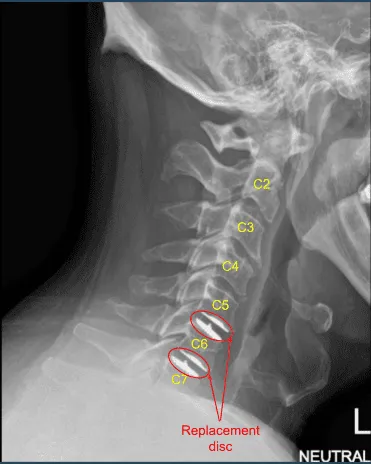

También se extirpó el PLL y se extirparon osteófitos posteriores usando Kerrison #1 y #2. Una vez realizada la discectomía, se nivelaron las placas terminales. Se utilizaba un separador vertebral para comprobar el aplanamiento de la superficie. Se utilizó una plantilla para el reemplazo del disco y se planeó un disco de 19 mm x 15 mm x 6 mm. El disco se insertó en el espacio del disco y se comprobó con el brazo en C, y se comprobó que era satisfactorio.

Se retiró el soporte del disco. Ahora, el pasador Caspar C7 fue retirado e insertado en C5. La distracción de C5-C6 se realizó utilizando el distractor de Caspar. La discectomía se realizó usando curette y Kerrison #1 mm y 2 mm. Se extirpó la LLP y se extirparon los osteófitos. Se realizó una foraminotomía exhaustiva de la C6 bilateral con el uso de los puñetazos Kerrison número 1 y 2.

El espacio del disco fue ampliado y se planificó un disco de 6 mm x 17 mm x 15 mm. El disco se abría, se insertaba en el espacio del disco y se comprobaba satisfactorio en la vista AP y lateral del brazo C mediante fluoroscopia. Al encontrarlo en una posición satisfactoria, se retiraron los pasadores de Caspar.